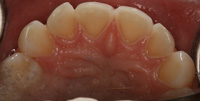

Lingual Veneers - Why? To restore worn-away enamel from acid erosion due to eating disorders.Lingual veneers are veneers that are placed on the inside, or lingual, surface of the front teeth. Rather than remove any healthy enamel from the remaining front and back sides of the teeth to do crowns, lingual veneers offer a conservative alternative for those who have experienced acid erosion, or tooth wear, of the lingual surfaces due to the detrimental effects of eating disorders such as bulimia. The goal is to build up and restore worn away teeth while preserving as much of the natural, beautiful and healthy tooth structure as possible. This strengthens and reinforces the tooth from further damage and drastically reduces sensitivity so a healthy diet and lifestyle can be resumed. Professional dental help for bulimia It is important to seek dental care if you have bulimia and to openly share with the dentist what is happening. Many dentists are caring professional people who understand the problems with bulimia and want to help. Without the dentist's help, the dental consequences of your bulimia can be severe. Dr. Berland can usually provide all of the dental services needed to restore the bulimic patient back to good dental health in a confidential and private manner. Additionally, Dr. Berland can help a bulimic patient manage the condition so that, even if they are continuing to have problems, the dental consequences of bulimia are lessened or eliminated. The Dallas Dental Arts services can be specially arranged for a bulimic patient so that all needed dental treatment can be intensively completed in a short period of time. This makes it possible for patients from out of town to complete their desperately needed dental care confidentially and in as few visits as possible. The Dallas Dental Arts can also assist in obtaining the funds for this care so everything that needs to be done can be completed. For more information on financial assistance, please click here. Dr. Berland has successfully cared for many patients suffering from bulimia and would be pleased to meet with you in a confidential consultation. Here, You can privately discuss your choices in dealing with your bulimia. Dr. Berland understands that you are struggling with bulimia and that it may take time to deal with the consequences of your bulimia. Privately speaking with Dr. Berland can be your first step in conquering your bulimia. Please consider calling (214)999-0110 and scheduling a consultation. You do not have to say why you are visiting, just that you would like a private consultation. If calling for an appointment is too embarrassing, you can first email Dr. Berland at drberland@dallasdentalspa.com or you can schedule a consultation and privately email him to let Dr. Berland know that you wish to talk about your bulimia. This young lady came to our office looking for a way to improve her smile, self-image and most importantly, her health. As a recovering bulimic patient, she had endured years of damage to her enamel from her previous history of eating disorders. In her case, the erosion wore all the way through her enamel and even into the soft, sensitive inner tooth layer, the dentin. She sought us out to find a way to restore her smile without further compromising the fragile condition of her teeth. Other dentists discussed filing her already thinned down teeth further and "strengthening" them with porcelain crowns. Our approach was completely different. Why take away more when you don’t have much to begin with? We recommended she try lingual resin veneers (on the backside of her teeth) followed by cosmetic one-stop bonding on the front and especially the edges of her teeth. This is a completely noninvasive and a purely additive procedure. She would be adding strength to her teeth, fortifying them rather than removing any of her remaining enamel, thereby reinforcing her teeth, improving her dental condition and creating the beautiful, yet natural, smile she desired. When the patient heard of this conservative treatment alternative, it made sense to her to preserve her teeth to maintain her health and restore her smile. Not only were the back sides of her teeth built out, length was added to replace what was worn over the years for a more youthful smile. After the no-shots, no-drilling, and no-pain appointment, her teeth were no longer sensitive to sweets, hot or cold. The patient was very pleased with her results. She not only gained a beautiful, new smile, but she also had a renewed confidence in herself and a reassurance of a healthier smile – and that means a healthier lifestyle as well! With all the focus of the media on diets, exercise equipment and personal care products, people are more concerned with their appearance and physical health than ever. In an effort to meet today's standard of beauty and "health", many people are quick to try the newest crash diet fad without ever realizing that this may, in fact, be the incorrect way to diet. These crash dieters who excessively fast, or try every new trend, tend to have a lack of, or decrease in certain vitamins, most notably Vitamins D, B-12 and calcium. They also tend to lack certain minerals and proteins in their diets. These are very important vitamins especially for the health of the teeth and gums. What can occur is that dieters tend to have a diet high in fruits which may contain a high content of natural sugars. These sugars tend to decay and erode the enamel of the teeth. Mints, used to combat the bad breath associated from Ketosis caused by an unbalanced protein diet and "so-called" Power Bars can further decay the teeth. Dieters also tend to take diet pills that may cause a decrease in saliva flow as a side effect. This decrease in saliva flow tends to increase the acid levels in the mouth which may cause an increased level of cavity formation. Antidepressants and decongestants have the same effect. Dr. Berland cares about the health and well-being of his patients. If you are currently on a diet that restricts certain food groups and/or you are taking a supplement or prescription diet aid, your oral health may compromised and in need of attention. Click here to see an example of the effects of eating disorders on your teeth. Please discuss with Dr. Berland at your next appointment any of these changes in diet or methods of weight control and any problems or discomfort you may be experiencing in your teeth and gums. Dr. Berland has many conservative measures to prevent and alleviate these conditions. Preventing a dental situation before it becomes a problem can save not only your teeth-- but, discomfort, time, money and your health. |

Lingual Veneers - Why? To restore worn-away enamel from acid erosion due to eating disorders.